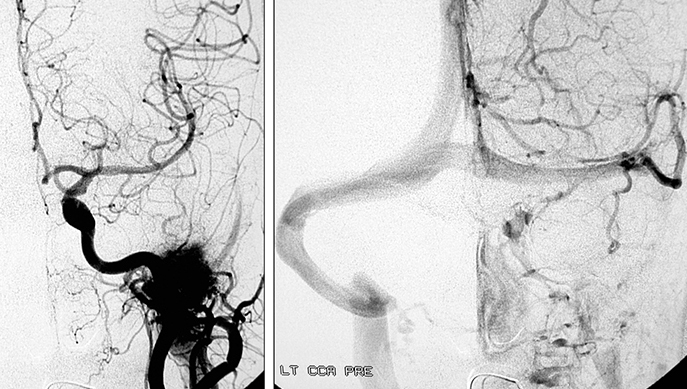

Aνάλογα με το μέγεθος και τις επεκτάσεις, αιματώνονται από διάφορετικές αρτηρίες. Στο αρχικό στάδιο που ο όγκος εντοπίζεται στον πρόσθιο ρινοφάρυγγα και την οπίσθια ρινική κοιλότητα, η αιμάτωση γίνεται από το τελικό τμήμα της έσω γναθιαίας αρτηρίας (με τον σφηνουπερώιο κλάδο να τροφοδοτεί το ρινικό τμήμα, και τον πτερυγοειδή κλάδο το ρινοφαρυγγικό τμήμα του).